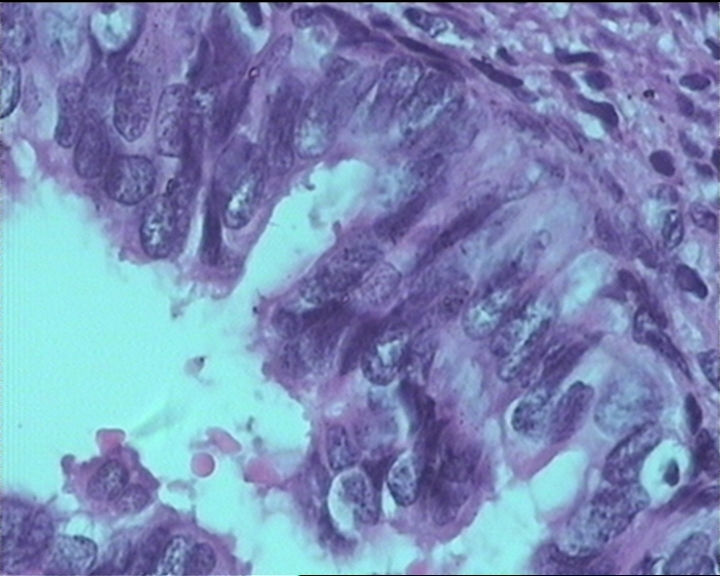

54岁女性,临床“宫颈息肉”送检;巨检:组织一块1。5*1CM,灰红。

细胞及腺体均有异形,图6、11、16象有纤维间质反应,考虑高级别上皮内瘤变/原位癌,腺癌不能除外。

输卵管粘膜化生

It is benign. Benign endocervical polyp with tubal metaplasia.

杨老师说它是良性的,是个颈管内膜息肉伴输卵管上皮化生,良性

Thanks for providing more photos from this case. If you are really concerning this case for dysplasia which is in the differential diagnosis, please perform a p16 immunohistochemistry to have a peaceful mind.

Sternberg病理学上诊断宫颈原位腺癌的标准是腺体的上皮去粘液分化,呈乳头状或筛网状增生,核分裂易见,这例显然达不到此标准。此例还是归入到腺上皮不典型增生为好。